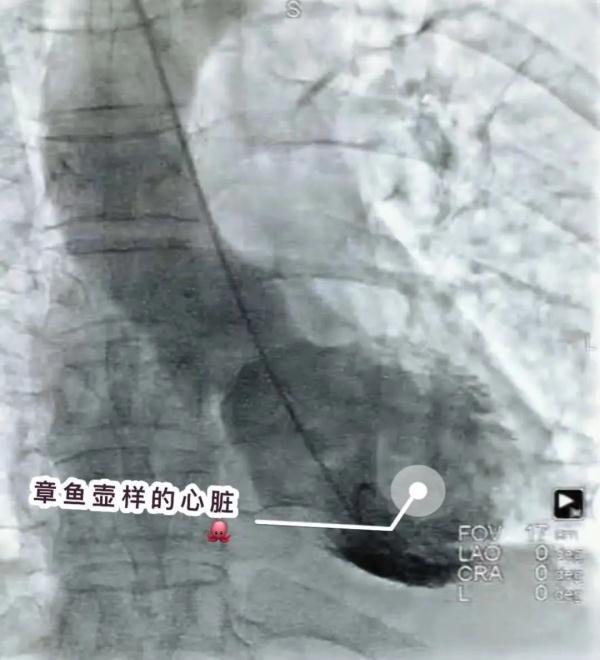

为了确诊病情,周阿姨被转至浙江省杭州市第一人民医院,行急诊冠脉造影术。造影显示周阿姨左心室形态酷似“章鱼壶”,就是临床上少见的“心碎综合征”。所幸就医及时,周阿姨最终转危为安。

心碎综合征又可称作心尖球化综合征、应激性心肌病。左心室外型看起来很像传统捕捉章鱼用的章鱼壶,也被称之为“章鱼壶心肌病”。